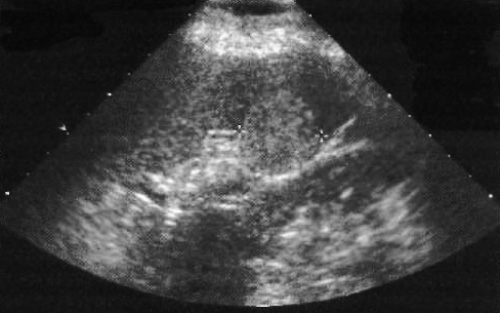

Ультразвуковая картина гемангиомы селезенки имеет разные варианты: образование может быть эхогенным и хорошо ограниченным, однако в самих гемангиомах могут визуализироваться мелкие анэхогенные очаги, что придает образованию смешанный вид (кистозный или солидный). Размеры очагов в большинстве случаев небольшие, но в иногда могут достигать до 17 см (фото 1).

Фото 1. Гемангиома селезенки. Курсорами обозначена типичная гемангиома: гиперэхогенное образование с четкими границами